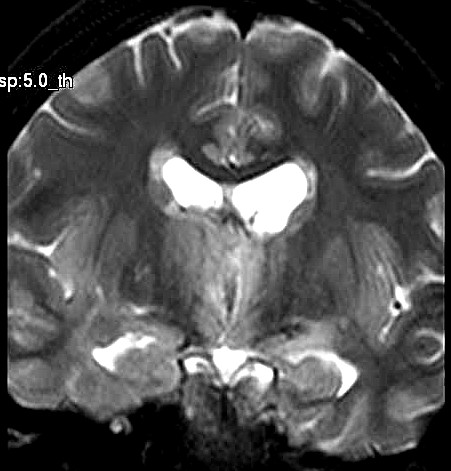

| Fem. 17a. |

| Nódulo sólido homogêneo preenchendo o III ventrículo, com limites precisos, com hipossinal em T1 e hipersinal em T2 e FLAIR, que se impregna por contraste paramagnético. Lesão menor implantada no assoalho do IV ventrículo provavelmente representa disseminação por via liquórica. |

| F. 17a. Tumor teratóide rabdóide atípico de III ventrículo. RM | HE | VIM, GFAP | HHF35, desmina, 1A4 | AE1AE3, EMA |